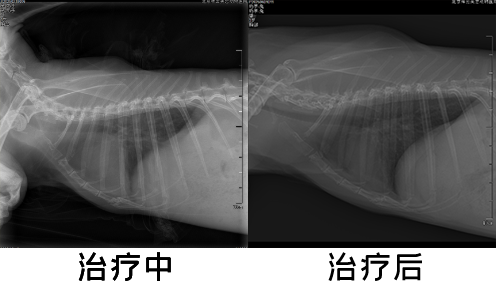

★病例名称:垂耳兔心脏病

1、患宠品种:垂耳兔

2、患宠名字:奶茶

3、患宠年龄:3岁6个月

4、患宠性别:雄

5、体格检查:就诊前一天突然觉得呼吸困难,腹式呼吸。就诊当天精神食欲不佳、大便颗粒小、鼻孔张开幅度大,听诊心音弱、心率慢。

6、难点描述:患宠呼吸困难,有胸腔积液,且应激,治疗操作风险较高。

7、诊断过程:体格检查后进行DR、血检、心脏超声、CT等检查,确诊兔子患心脏病。

8、治疗方法:经与主人沟通后,放置胸导管排出胸腔积液,安排口服用药,入住ICU实时监测。

9、预后情况:经过悉心治疗,患宠胸腔积液恢复,呼吸、饮食、精神恢复,为巩固治疗效果需要继续口服药治疗。

治疗中-后.png